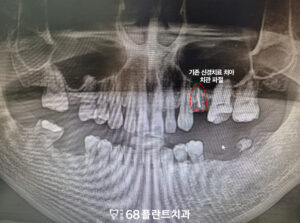

위 환자분께서는

왼쪽 위 신경치료 했었던 치아가

충치로 인해 부러져

철산역치과 이편한68플란트에

내원해 주셨는데요.

파노라마 사진을 통해 진단해 보니,

왼쪽 위 치아는 머리 부분이

완전히 부러져 저작 기능을

전혀 할 수 없는 상태였습니다.

다른 부위도 치아가

상실되어 있었습니다.